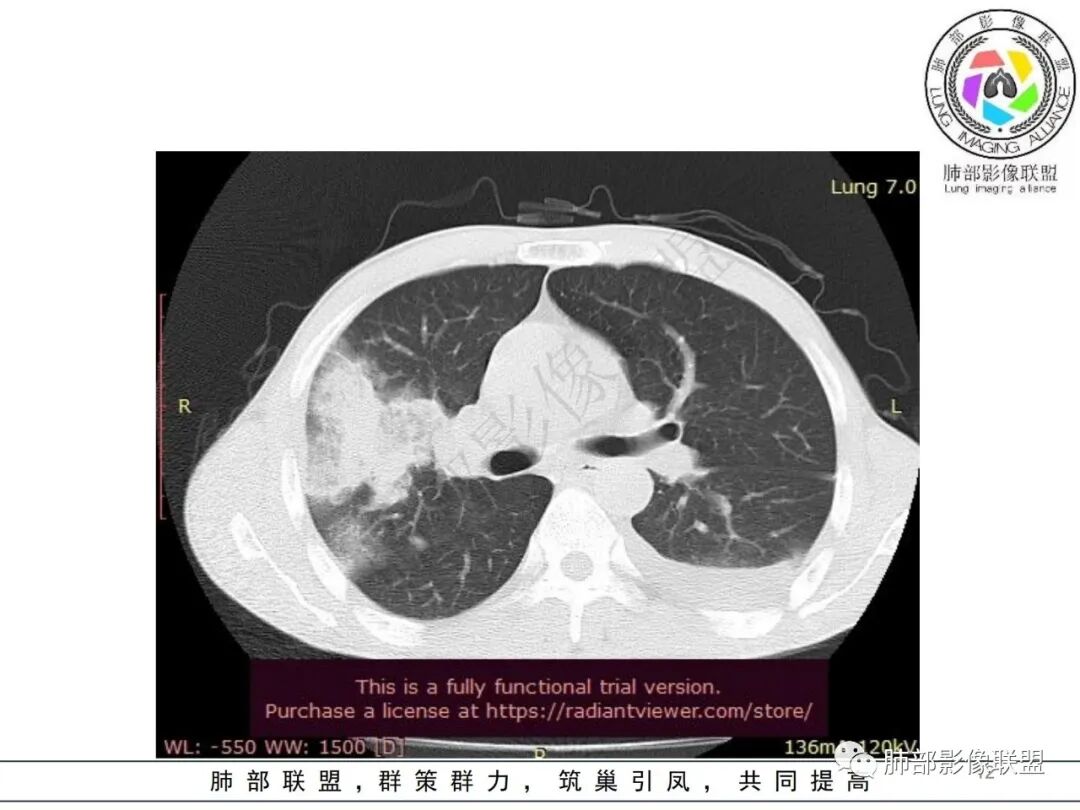

双肺多发大小不等结节影,边缘伴有磨玻璃影,边界欠清,部分与血管束相连,支气管似有穿行病灶内,结节有融合,左肺下叶厚壁空洞,伴有反晕征,左侧胸水,临床中年男性,发热40℃,CRP增高,感染性病变,1:类鼻疽伯克霍尔德菌(好发海南,影像表现也符合)

影像:双肺多发结节、实变影,大部分病灶边界不清,分布相对随机,左下肺坏死空洞形成,伴左侧胸水。

影像表现:双肺弥漫分布斑片影、实变影、磨玻璃影、结节影,晕征、反晕征,随机分布,部分病灶空洞形成前兆,左侧胸腔积液。

两肺多发斑片状实变影,周围GGO

主体还是沿支气管,大片叶段性分布

影像上急性感染,大叶性病变为主

单凭影像:鹦鹉热、军团要考虑,因为内部无坏死,非典型气道为主

我纠结的是,这是气道来源还是血播,如果血播加上海南下田,优先类鼻疽,如果气道,军团也要考虑,只是没见过军团反晕,除非免疫缺陷,混合感染。另外肺克,肺克好像气血皆可,后面反晕出洞,如果没有海南,也要考虑吧,肺克也是免疫妥协相关菌

这一类表现等于是病灶没有沿气道趋势,不支持以肺实质、支气管的分布区域,我认为是沿气道到播散,间质蔓延为主

这是比较早的病灶,其他的比较晚的病灶

觉得后面那些符合血道,左下的更符合气道的

影像表现:双肺多发结节、实变影,大部分病灶边界不清,随机分布趋势,左下肺“反晕征”,似有形成空洞趋势。左侧胸腔积液。治疗后复查 ,大部分病灶吸收好转,呈较为典型血播分布,肝脏低密度块影,边界不清,符合肝脓肿。